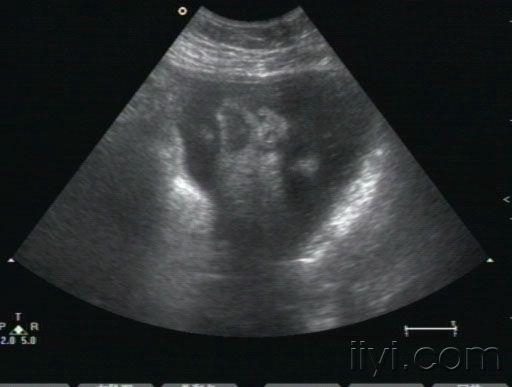

胎儿心包积液

• 孕38周,10天以前在多家医院检查胎儿正常。近一周来自觉腹胀,下坠。发现胎儿心包积液,并且右室壁好象很厚。胎儿生下来后,临床医生没有听到杂音,遗憾的是孩子也没来检查心脏。我们没有开展胎儿心脏,请各位专家帮忙看下,到底是什么原因,胎儿右室壁增厚考虑什么病,为什么生后没有杂音呢?